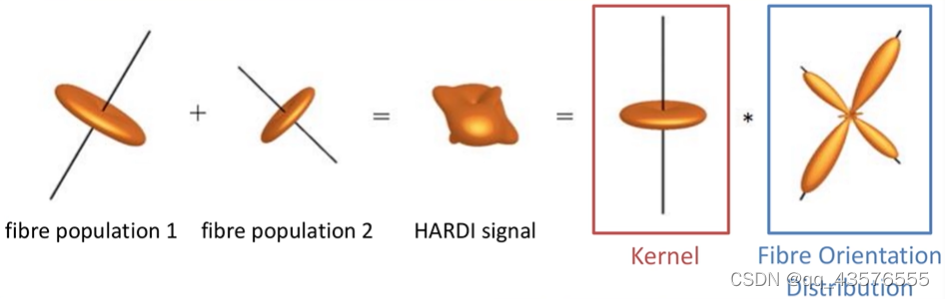

tensor2metric: [100%] computing metrics由于弥散像体素比纤维大得多,无法反映神经纤维束的真实走向,这里我们不用dt.mif估算神经的方向,因此使用constrained spherical deconvolution(CSD)算法,计算各个方向纤维束的贡献,这里的kernel称为反应函数

先对灰质、白质、脑脊液分别进行反应函数kernel的估计,得到三个反应函数,并且可以选择输出估计时用到的体素,可以使用shview查看反应函数(3个b值0/1000/2000的都可以看)

dwi2response: Deleting scratch directory (/home/hzhb/Fengz/demo/dwi2response-tmp-MWHD2Y/)得到反应函数后,我们估算FOD,该步骤大概需要几分钟,可以用mrview查看得到的文件dwi_gmCsd.mif等,得到每个体素的不同纤维走向的贡献程度(可能性大小)